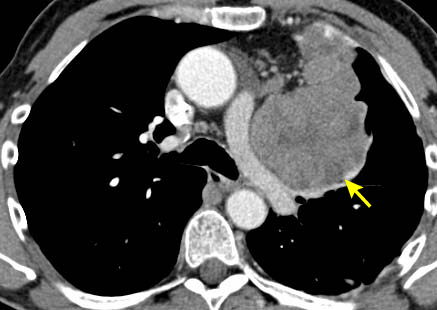

[Figure caption and citation for the preceding image starts]: Tomografia computadorizada (TC) do tórax mostrando timoma com encarceramento e invasão da veia inominada esquerdaDo acervo de Cameron Wright, MD; usado com permissão [Citation ends].